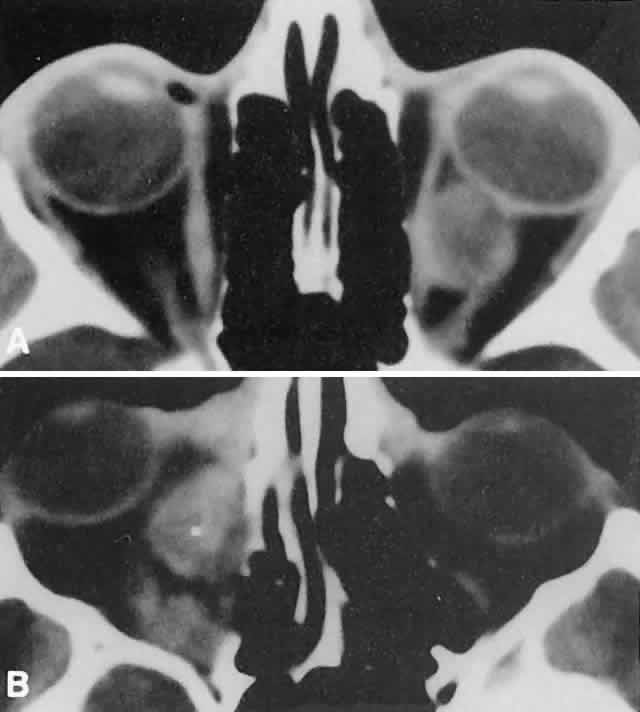

Within the orbit, rhabdomyosarcoma occurs most often, but not exclusively, in the superior nasal quadrant, with downward and outward displacement of the globe. CT scans show the topography of the orbital mass (Fig. 1A), as well as the possible extension into adjacent bone, paranasal sinuses, or the intracranial cavity. The circumscription that may be noted on CT is relative, because the lesion is not encapsulated and microscopically infiltrates normal tissue. Echography shows internal echoes of low-to-medium amplitude. Because the cellular tumor absorbs acoustic energy, the amplitude of the spikes falls off somewhat through the lesion (see Fig. 1B and C). MRI can help define the tumor's relationship to extraocular muscles (Fig. 2).

Fig. 1. A. Proptosis and downward, outward globe displacement developed over 2 days in a 3-year-old girl. A homogeneous mass fills the superomedial orbit. B. Contact B-scanning shows a relatively well-circumscribed mass with uniform internal echoes. C. Contact A-scanning shows the internal reflectivity to be of low to medium amplitude, consistent with a sarcomatous lesion. Biopsy results confirmed the diagnosis of rhabdomyosarcoma.